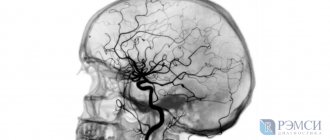

- Магнитно-резонансный метод позволяет визуализировать продольные и поперечные срезы, получая точное изображение сосудов не только головного, но и спинного мозга с определением параметров тока крови.

МРТ при обследовании головного мозга – незаменимый метод исследования, позволяющий точно установить ряд патологий мозговых оболочек, собственно мозговой ткани и сосудов, а также нервных сплетений. КТ головы обычно делают для оценки здоровья твердых оболочек, костей черепа, стыка основания черепа и позвоночника, лицевых костей.